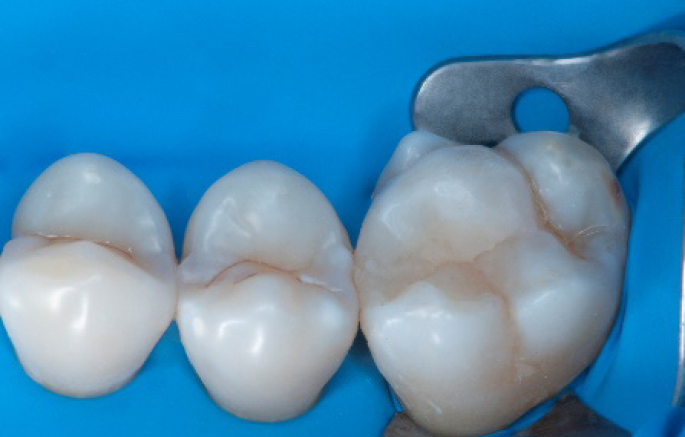

The situation after rubber dam removal.

Step 13:

Occlusal check

Step 14:

2 weeks control